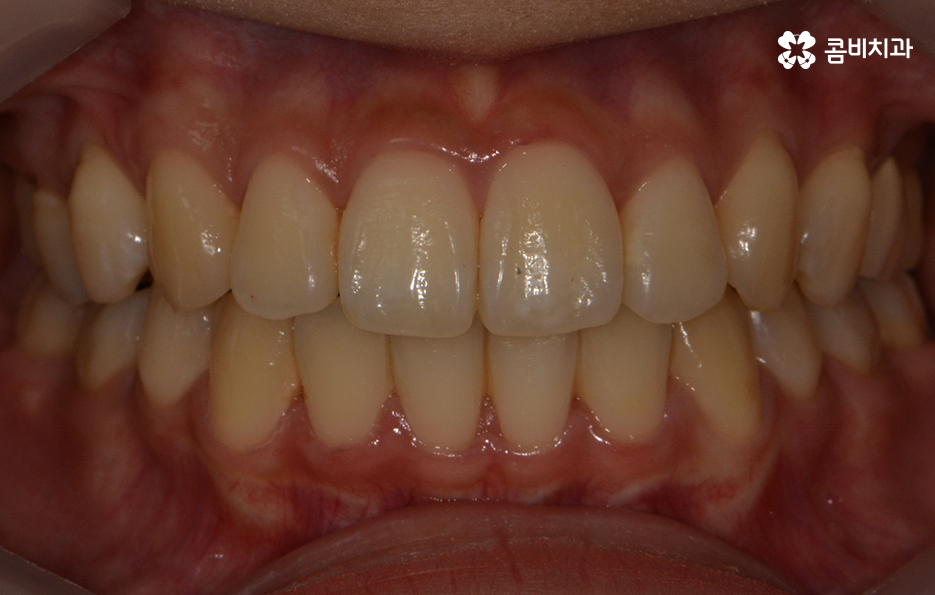

콤비교정이 완료된 모습이며 가지런한 치열 및

얼굴형과도 자연스럽게 어울리는 결과를 얻는 모습입니다.

치열 뿐 아니라 교합이 잘 맞물리고 있는 결과